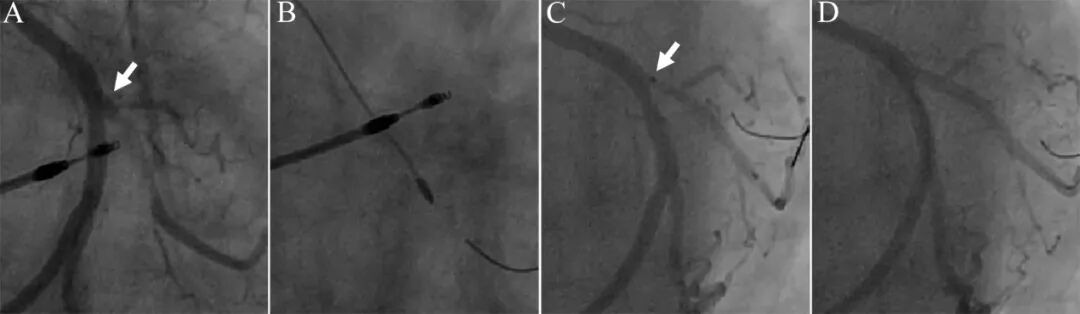

48岁女性,运动后胸痛3年,加重2周,肌钙蛋白轻微升高,诊断为NSTEMI。造影提示前降支中段狭窄50%,第一对角支开口狭窄95%(A)。对角支为靶病变。首先尝试球囊处理,2.5×10mm切割球囊处理后(B),2.5×15mm药物球囊扩张60秒(C),造影提示对角支开口明显夹层形成(D)。鉴于对角支比较粗大,夹层累及开口部,决定采用单支架Crossover置入。前降支近段-对角支近段植入3.0×18mm药物洗脱支架(E),近端POT。造影提示前降支狭窄有所加重(F),提示脊移位或斑块移位可能。二个3.0mm高压球囊对吻扩张(G),然后前降支局部3.0×15mm药物球囊扩张30秒处理。最后结果良好(H)。